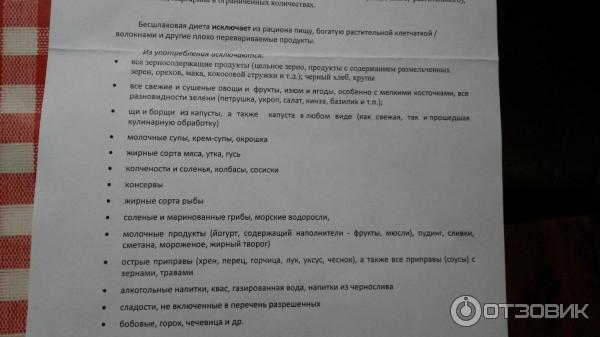

Подготовка к ирригоскопии: необходимые препараты